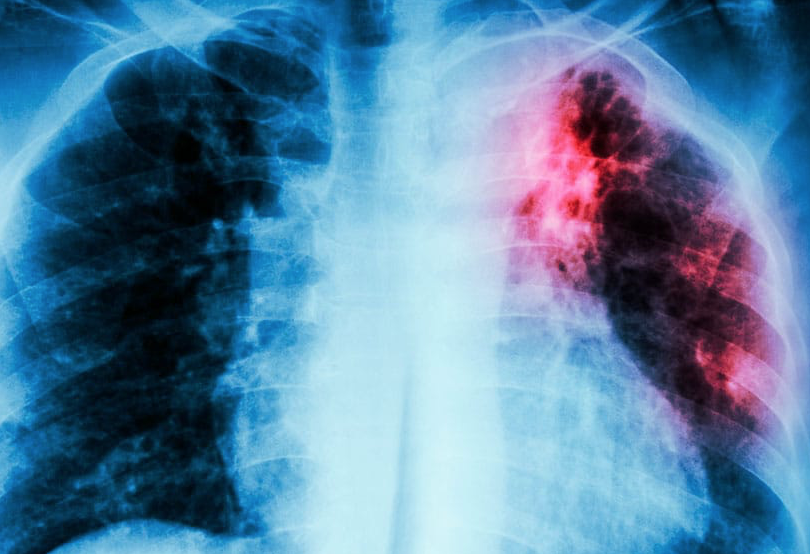

En la región de las Américas se estima que unas 350.000 personas enfermaron de tuberculosis y alrededor de 30.000 fallecieron por esta causa en 2024. De estas muertes, cerca del 29% se atribuyeron a la coinfección entre tuberculosis y VIH.

Todavía existe una brecha importante en el diagnóstico: se estima que unas 77.000 personas con tuberculosis (alrededor de 1 de cada 4) no fueron diagnosticadas en 2024, lo que significa que muchas siguen sin recibir tratamiento y pueden continuar transmitiendo la enfermedad.

Diagnosticar la tuberculosis a tiempo reduce la transmisión de la bacteria a otras personas y permite iniciar el tratamiento antes de que la enfermedad cause complicaciones más graves. Cuando el diagnóstico se retrasa, la infección puede progresar y diseminarse a otros órganos del cuerpo, además de aumentar el riesgo de secuelas a largo plazo. La detección temprana sigue siendo una de las estrategias más efectivas para avanzar hacia la eliminación de la enfermedad.